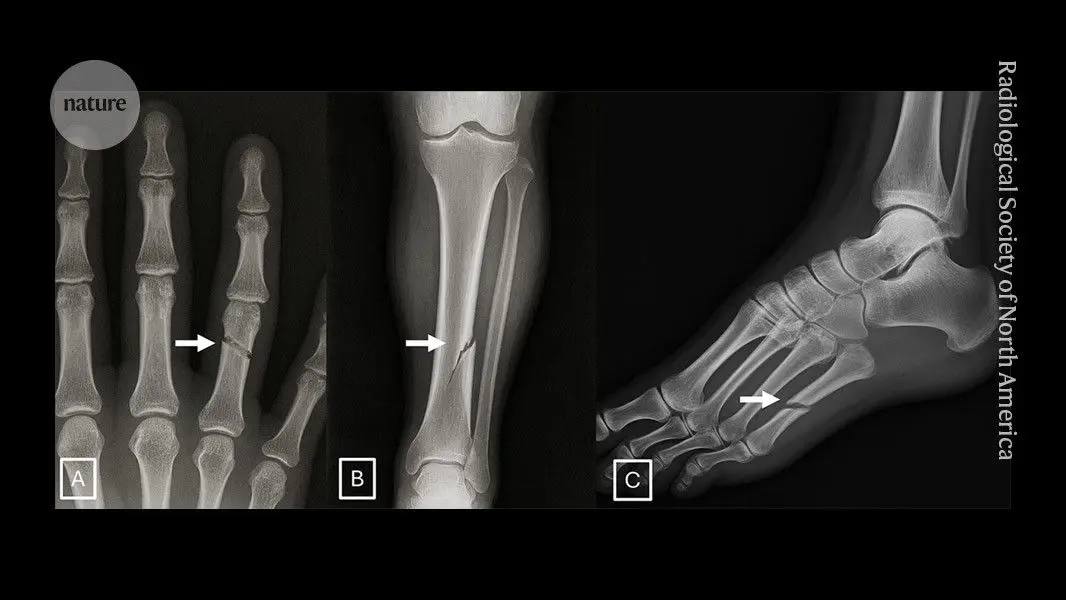

Radiological Society of North AmericaMar 24 2026 Neither radiologists nor multimodal large language models (LLMs) are able to easily distinguish artificial intelligence (AI)-generated "deepfake" X-ray images from authentic ones, according to a study published today in Radiology, a journal of the Radiological Society of North America (RSNA). The findings highlight the potential risks associated with AI-generated X-ray images, along with the need for tools and training to protect the integrity of medical images and prepare health care professionals to detect deepfakes. The term "deepfake" refers to a video, photo, image or audio recording that appears real but has been created or manipulated using AI. Our study demonstrates that these deepfake X-rays are realistic enough to deceive radiologists, the most highly trained medical image specialists, even when they were aware that AI-generated images were present. This creates a high-stakes vulnerability for fraudulent litigation if, for example, a fabricated fracture could be indistinguishable from a real one. There is also a significant cybersecurity risk if hackers were to gain access to a hospital's network and inject synthetic images to manipulate patient diagnoses or cause widespread clinical chaos by undermining the fundamental reliability of the digital medical record." Mickael Tordjman, M.D., lead study author, post-doctoral fellow, Icahn School of Medicine at Mount Sinai, New York Seventeen radiologists from 12 different centers in six countries (United States, France, Germany, Turkey, United Kingdom and United Arab Emirates) participated in the retrospective study. Their professional experience ranged from 0 to 40 years. Half of the 264 X-ray images in the study were authentic, and the other half were generated by AI. Radiologists were evaluated on two distinct image sets, with no overlapping between the datasets. The first dataset included real and ChatGPT-generated images of multiple anatomical regions. The second dataset included chest X-ray images-half authentic and the other half created by RoentGen, an open-source generative AI diffusion model developed by Stanford Medicine researchers. When radiologist readers were unaware of the study's true purpose, yet asked after ranking the technical quality of each ChatGPT image if they noticed anything unusual, only 41% spontaneously identified AI-generated images. After being informed that the dataset contained synthetic images, the radiologists' mean accuracy in differentiating the real and synthetic X-rays was 75%. Individual radiologist performance in accurately detecting the ChatGPT-generated images ranged from 58% to 92%. Similarly, the accuracy of four multimodal LLMs-GPT-4o (OpenAI), GPT-5 (OpenAI), Gemini 2.5 Pro (Google), and Llama 4 Maverick (Meta)-ranged from 57% to 85%. Even ChatGPT-4o, the model used to create the deepfakes, was unable to accurately detect all of them, though it identified the most by a considerable margin compared to Google and Meta LLMs. Radiologist accuracy in detecting the RoentGen synthetic chest X-Rays ranged from 62% to 78% and the LLM models' performance ranged from 52% to 89%. There was no correlation between a radiologist's years of experience and their accuracy in detecting synthetic X-ray images. However, musculoskeletal radiologists demonstrated significantly higher accuracy than other radiology subspecialists. The study identified common features of synthetic X-rays. "Deepfake medical images often look too perfect," Dr. Tordjman said. "Bones are overly smooth, spines unnaturally straight, lungs overly symmetrical, blood vessel patterns excessively uniform, and fractures appear unusually clean and consistent, often limited to one side of the bone." Recommended solutions to clearly distinguish real and fake images and help prevent tampering include implementing advanced digital safeguards, such as invisible watermarks that embed ownership or identity data directly into the images and automatically attaching technologist-linked cryptographic signatures when the images are captured. "We are potentially only seeing the tip of the iceberg," Dr. Tordjman said. "The logical next step in this evolution is AI-generation of synthetic 3D images, such as CT and MRI. Establishing educational datasets and detection tools now is critical." The study's authors have published a curated deepfake dataset with interactive quizzes for educational purposes. Radiological Society of North America Journal reference: Tordjman, M., et al. (2026). The Rise of Deepfake Medical Imaging: Radiologists' Diagnostic Accuracy in Detecting ChatGPT-generated Radiographs. Radiology. DOI: 10.1148/radiol.252094. https://pubs.rsna.org/doi/10.1148/radiol.252094

The study identified telltale characteristics of synthetic images that can help with detection. "Deepfake medical images often look too perfect," Tordjman explained. "Bones are overly smooth, spines unnaturally straight, lungs overly symmetrical, blood vessel patterns excessively uniform, and fractures appear unusually clean and consistent, often limited to one side of the bone"

2